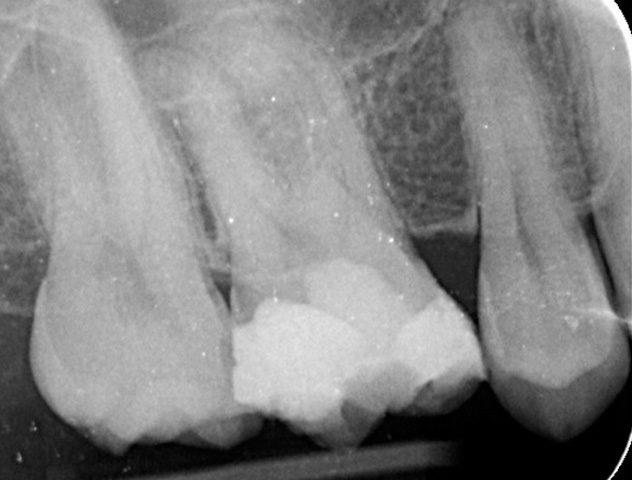

Gallery - Root Canal Treatment

Case 4

Before After